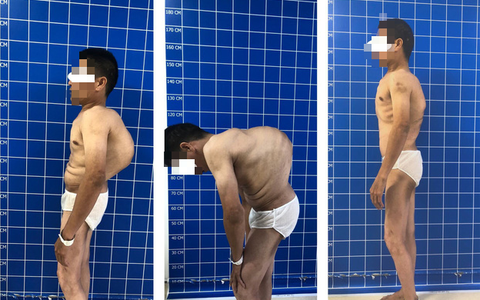

Bệnh viện Trung ương Quân đội 108 vừa điều trị thành công cho một bệnh nhân gù lưng nặng, góc vẹo rất lớn. Các bác sĩ đã cắt xương sườn, vén phổi nắn chỉnh chữa gù vẹo cột sống, giúp bệnh nhân có thể "nhìn thẳng" sau nhiều năm.